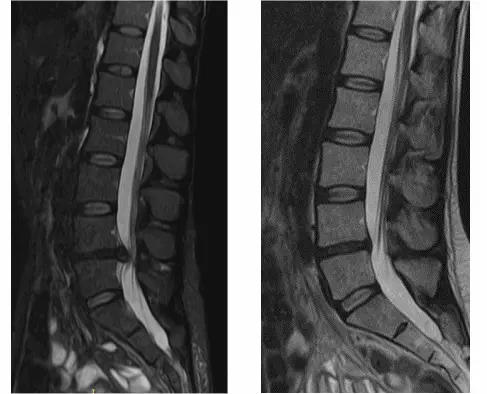

На МРТ показано излечение грыжи диска (до- и после лечения).

Контрольный МРТ, через 5 месяцев показал полное отсутствие грыжи диска (см. снимки Ирины ниже):

Обратите внимание на даты проведения МРТ в правом нижнем углу. МРТ исследования проведены на одном аппарате 1.5 теслы в клинике «Меддиагностика» в процессе лечения Ирины. МРТ позвоночника позволяет отследить динамику уменьшения грыжи диска.